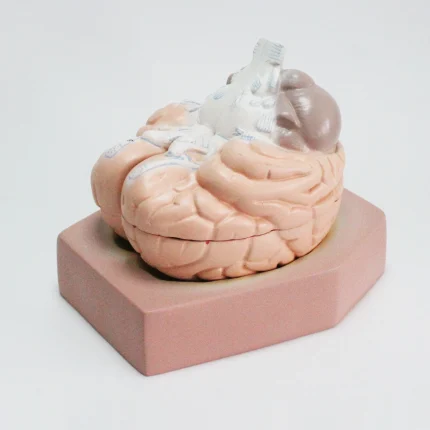

Modèle anatomique de cerveau humain

Modèle de cerveau humain

4 parties : (Fabriqué à partir de fibre de verre)

Modèle anatomique de cerveau humain

4 parties : (Fabriqué à partir de fibre de verre)

Ce cerveau est médialement divisé en deux parties, la moitié droite peut être démontée en frontal avec les lobes parentaux, le tronc cérébral avec les lobes temporaux et occipitaux en deux parties. Placé sur une base amovible avec Key Card numérotée.